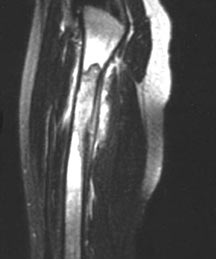

- May arise from any bone and any site within a bone (epiphyseal, metaphyseal, diaphyseal)

- Radiographically variable appearance: may appear benign (geographic) or malignant (permeative or moth eaten)